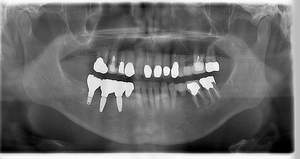

インプラント治療の症例4

レントゲン写真

- Befor

- After

| 年齢 | 50代・男性 |

| 主訴 | 部位:左下6番7番 主訴:左下奥歯腫れて痛い。 |

| 治療内容 | 左下6番抜歯、左下6番7番骨造成、インプラント埋入 |

| 治療費 | 合計:1,232,000円 ・内訳 診断料:55,000円 サージカルガイド2本:66,000円 GBR:110,000円×2本 埋入料:165,000円×2本 静脈内鎮静麻酔:77,000円 2次OPE:22,000円×2本 仮歯:55,000円×2本 上部構造(フルジルコニア):165,000円×2本 (2023年1月現在) |

| 治療期間 | 約8ヶ月 |

| 治療方針 | 元々支台歯に負荷がかかりやすいとされている延長ブリッジを抜歯し、1本単体でしっかりかめるようにインプラントを2本埋入した。骨吸収も進んでいたため、※GBR法で骨造成を同時に行った。 治療と並行して、全顎的な歯周病治療も行い、今後は歯周病が進行しないよう、こまめにメンテナンスに通っていただく。 |

| 特記事項 | ※1 GBR・・・骨再生誘導法。骨の高さや厚みを人工骨や人工膜などを使用し再生する方法 |

| 担当者所見 | 6番は歯根分割された被せ物が7番の欠損部との延長ブリッジとされており、強い咬合と歯周病も相まって負荷がかかり動揺し、歯として機能しなくなったため、抜歯となった。 |